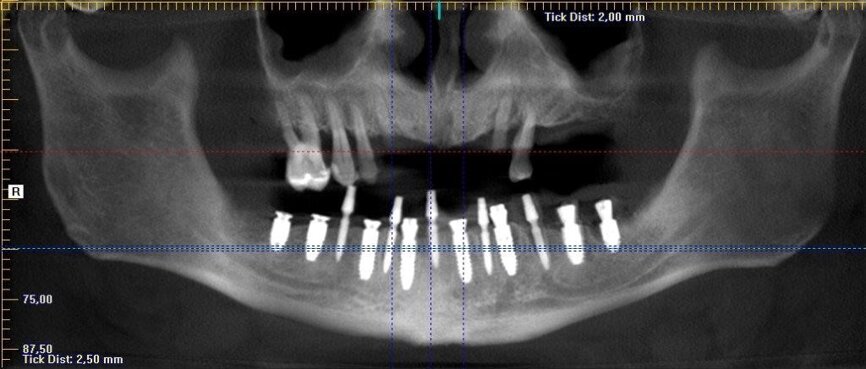

Wykonano CBCT, z którego wynikało, iż pacjent ma chorobę przyzębia. Zakwalifikowano wszystkie 10 zębów żuchwy do ekstrakcji. Zaplanowano zaopatrzenie pacjenta 8 implantami ICX oraz 5 implantami tymczasowymi Alpha Bio w celu wykonania pracy protetycznej tymczasowej bez obciążenia implantów docelowych ze względu na brak kontroli nad pacjentem w okresie wgajania implantów (zdjęcie CBCT oraz wewnątrzustne pacjenta). Za pomocą komputerowego systemu nawigacyjnego 3D został zaprojektowany szablon przytwierdzany 3 pinami do kości żuchwy w celu jego stabilizacji.